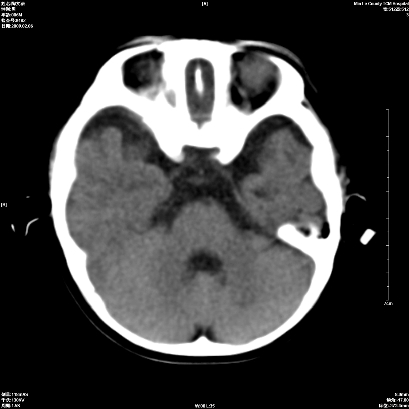

以下是引用wxq2008在2009-2-6 17:01:00的发言:[br]hie后遗症脑萎缩。

以下是引用学医在2009-2-6 21:45:00的发言:[br]hie后遗改变